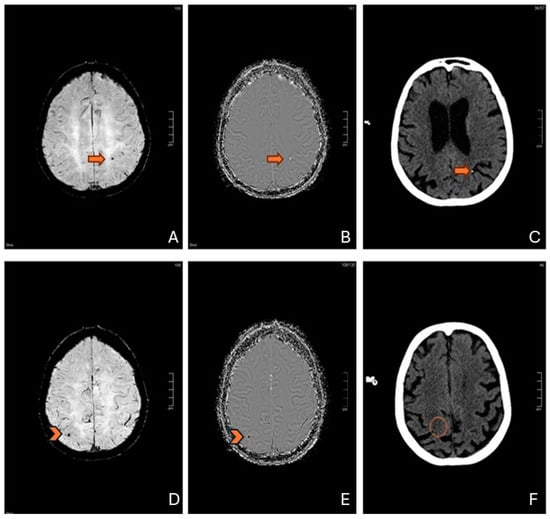

Meanwhile, seven [13,14,15,16,17,20,21] papers describe the majority of CMBs located in the lobar subcortical white matter (SWM), typically with a bilateral distribution (Figure 2).

Figure 2. Susceptibility-weighted imaging (SWI) of a patient after cardiac valve replacement demonstrating lobar and subcortical white matter microbleeds in the frontal and parietal lobes.